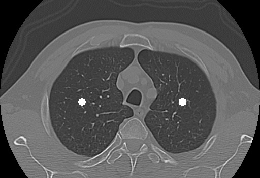

Chamado de método de inicialização automática de contornos ativos aplicados à segmentação pulmonar em imagens tomográficas, a nova carta patente trata-se de um artifício computadorizado que permite a segmentação dos pulmões em exames de TC do tórax, isto é, ele realiza o contorno da imagem dos pulmões e então isola a imagem do órgão para análise a ser feita pelo médico. Esse processo, em geral, é demorado, mas, com o novo método, pode ser concluído em menos de dois minutos, permitindo ainda separar mais de dois objetos de interesse na imagem.

Inventor responsável pela patente, o Prof. Paulo César Cortez, do Departamento de Engenharia de Teleinformática (DETI), explica que um exame de TC de tórax possui, em geral, cerca de mil imagens. Além disso, no caso de análise do exame para investigação de doenças pulmonares, o médico especialista (radiologista ou pneumologista) necessita visualizar somente a parte que corresponde aos pulmões (área de interesse) para cada uma das imagens que compõe o exame.

"Portanto, segmentar os pulmões em todas as imagens do exame é fundamental para a identificação de doenças no interior dos pulmões. Assim, nosso invento permite que o computador separe os pulmões em todas as imagens de um exame de TC do tórax", esclarece. Ele assegura que o invento soluciona a primeira tarefa de qualquer sistema de análise de imagens de TC dos pulmões, permitindo a reconstrução em três dimensões do órgão para a detecção dos nódulos e quaisquer outras análises necessárias ao diagnóstico médico.

Segundo o professor, o método pode ser usado na análise de imagens de TC do tórax para identificação e quantificação de doenças pulmonares como pneumonia, enfisema, doença pulmonar obstrutiva crônica (DPOC), entre outras.